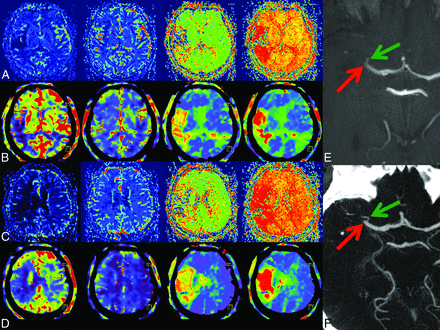

1) Case example. In rows A and C, MRP; in B and D, FD-CTP parameter maps (left to right: CBF, CBV, MTT, and TTP) are displayed. A and B and C and D are corresponding MRP and FD-CTP images. Due to an MCA occlusion, there is a significant perfusion deficit in all parameter maps. The MCA occlusion was visible in either MRA (E, red arrow) or in FD-CTA (F, red arrow) volume-rendering technique reconstruction.

Review of the volume-rendering technique/MIP reconstructions of the vascular images from both FD-CTA and MRA revealed that all occlusions seen on MRA images could also be recognized in FD-CTA reconstructions. The reviewers identified MCA occlusions (5 right, 7 left MCA occlusions, all TICI 3) in all cases (Figs 3F and 4F).